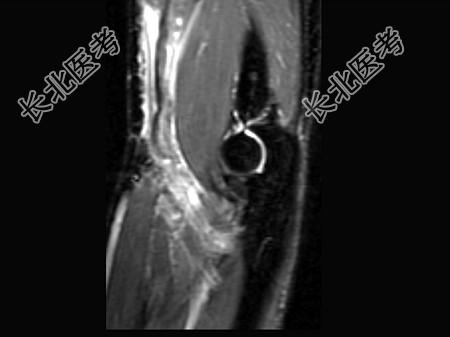

- 单项选择题女,44岁, 有外伤史,上臂远端疼痛, 结合图像,最可能的诊断是 ( )

D、肱二头肌腱远侧局部裂伤